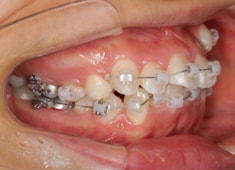

治療後(2年後)

治療開始から11ヶ月後